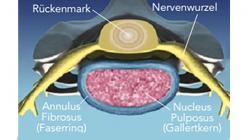

Bandscheiben sind flexible, faserknorpelige Verbindung, die als Stoßdämpfer zwischen den Wirbel dienen.

Mit zunehmendem Lebensalter kann es zu verschleißbedingten Rissen am äußeren Ring der Bandscheibe (Faserring) und zu einem Austritt des gallertartigen Kerns kommen. Dieser kann die benachbarten Nervenwurzeln oder das Rückenmark zusammendrücken und zu lokalen oder ausstrahlenden Schmerzen in den Armen und Beinen, ggf. auch mit Sensibilitätsstörungen und motorischen Ausfällen, führen.